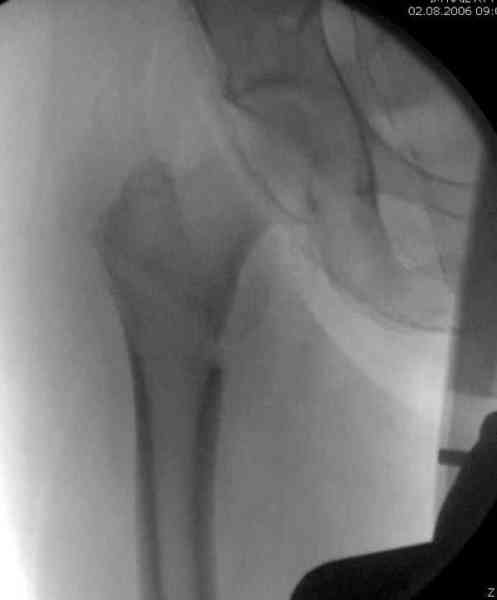

Здесь сканнированные снимки импланта и операционные снимки больной.

На этом снимке процесс компрессии нижним болтом.